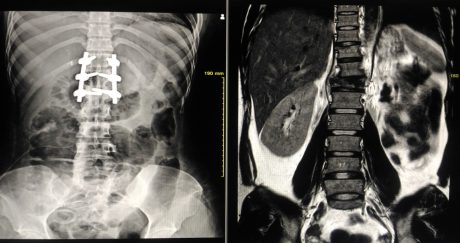

Despite this, the underlying cause remained undiagnosed and three weeks later, he collapsed at home. On emergency scanning at hospital, he was found to have a cervical spinal abscess. He underwent emergency cervical spinal surgery, including the insertion of metalwork. RG remained in hospital for seven months, and on discharge, he was noted to have a T3 ASIA C paraplegia with minimal improvement in hand grip.